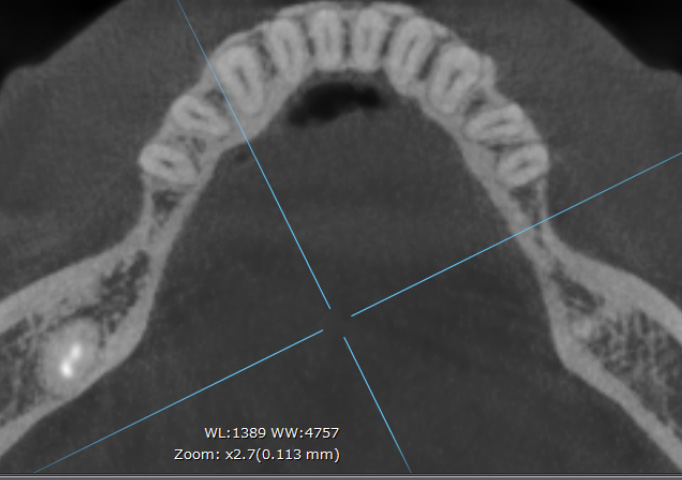

インプラント周囲の骨量を

確保した設計例

CT(アキシャル像)で確認すると、天然歯と比べて、インプラント周囲には計画的に骨量を確保していることが分かります。

これは周囲炎リスクを下げるために、埋入ポジションと骨のバリアを意識して設計しているためです。

※症例により条件は異なります。